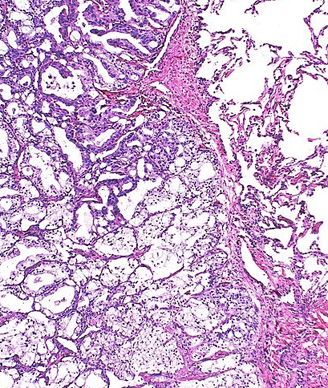

Metastatic prostatic adenocarcinoma; source: CFCF, Wikimedia Commons

A pooled analysis of five phase III clinical trials suggests that the site of a metastatic castration-resistant prostate cancer (CRPC) patient’s metastases can predict overall survival following treatment with docetaxel. CRPC patients with liver metastases had the worst overall survival-a median of 12.1 months. Those patients with lung metastases fared slightly better with a median overall survival of 16.5 months. Patients with bone metastases, but no visceral metastases had relatively better outcomes-a median overall survival of 20.3 months.